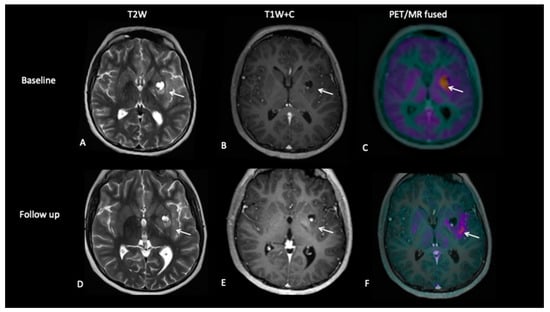

- Patient 2: Early Response Assessment

A 13-year-old female with a large tumour involving left thalamus and basal ganglia, infiltrating into the adjacent white matter, insular cortex and left aspect of the upper brain stem underwent a biopsy of the thalamic component, which confirmed high-grade astrocytoma with a mutation of the variant H3.3 gene. An early response assessment scan 6 weeks after completion of chemoradiotherapy demonstrated no residual enhancement in the tumour, but FDOPA PET showed residual tracer distribution consistent with residual metabolically active disease (Figure 5).

Figure 5.

At baseline, there is non-enhancing tumour involving the left basal ganglia (A,B) with 8F-fluorocholine (FCho) and 18fluoro-L-phenylalanine (FDOPA) avidity (C). Follow-up imaging shows residual non-enhancing tumour (D,E) reported as stable disease, but FDOPA PET demonstrates reduced uptake (F) consistent with metabolic partial response.